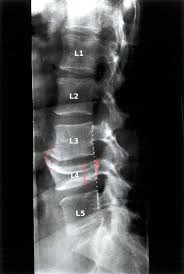

A transverse process fracture at the level of l5 is a surrogate marker of vertical instability of the pelvic fracture due to the attachment of the iliolumbar ligaments. Possible causes, signs and symptoms, standard treatment options and means of care and support. Transverse processes are used as lever arms by the deep spinal muscles to maintain posture and to induce rotation and lateral bending. It may occur as an avulsion fracture due to strong contracture of the muscles. Although the fracture is not associated with spinal cord damage and neurological deficits, the extreme force of the injury can cause visceral injuries and internal hemorrhage. The presence of other injuries might also be assessed due to the level of force needed to break the transverse process. In 78% of transverse process fractures, ct scanning showed that the fracture extended into the transverse foramen. Transverse process fractures caused by stress are likely under detected since even an acute transverse process fracture requires a high index of suspicion to be correctly identified(4,7). Here is an example of a patient with a benign looking transverse process fracture with an associated significant injury to the back. Transverse process fracture you have fractured a transverse process. Thoracic transverse process fractures (ttpfs) are injuries that go unnoticed during traditional autopsies, as demonstrated by a lack of medicolegal publications regarding ttpfs. We retrospectively reviewed the reports of lumbar spine and abdominopelvic ct scans from 2017 and 2018 to classify the types of spine fractures, their mechanism of injury, treatment and. Up to 60% of lumbar transverse process fractures identified on ct will be missed on plain radiographs.

However, postmortem computed tomography (pmct) has made detection of this type of injury easy. There are two transverse processes that extend off each vertebra in the details: What is a transverse process fracture? It may occur as an avulsion fracture due to strong contracture of the muscles. It occurs as a result of sudden and extreme trauma. If ct confirms isolated injury lateral flexion/extension views are indicated to rule out dynamic instability. Vertebral angiography, performed in eight patients with fractures involving the transverse foramen, showed dissection or occlusion of the vertebral artery in seven (88%) instances. This part extends out from the side of the main body of the bone (called the vertebral body). A transverse process fracture at the level of l5 is a surrogate marker of vertical instability of the pelvic fracture due to the attachment of the iliolumbar ligaments. We retrospectively reviewed the reports of lumbar spine and abdominopelvic ct scans from 2017 and 2018 to classify the types of spine fractures, their mechanism of injury, treatment and. Up to 60% of lumbar transverse process fractures identified on ct will be missed on plain radiographs. In 78% of transverse process fractures, ct scanning showed that the fracture extended into the transverse foramen. Transverse process fractures identified on helical computed tomography (ct) scans without the presence of any other fracture or.